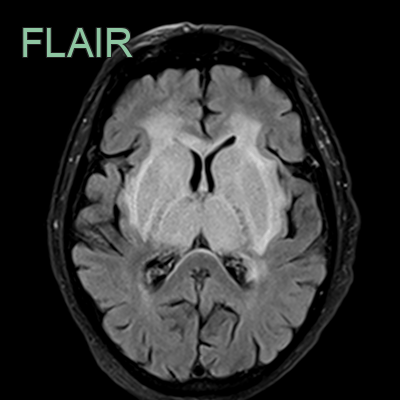

- 65-year-old patient on treatment for metastatic lung cancer.

- CT showed hyperdensity in the straight sinus, vein of Galen and internal cerebral veins.

- These vessels did not enhance on the CTV.

- MRI the next day showed hyperintensity and swelling of the deep grey structures and the capsular white matter.